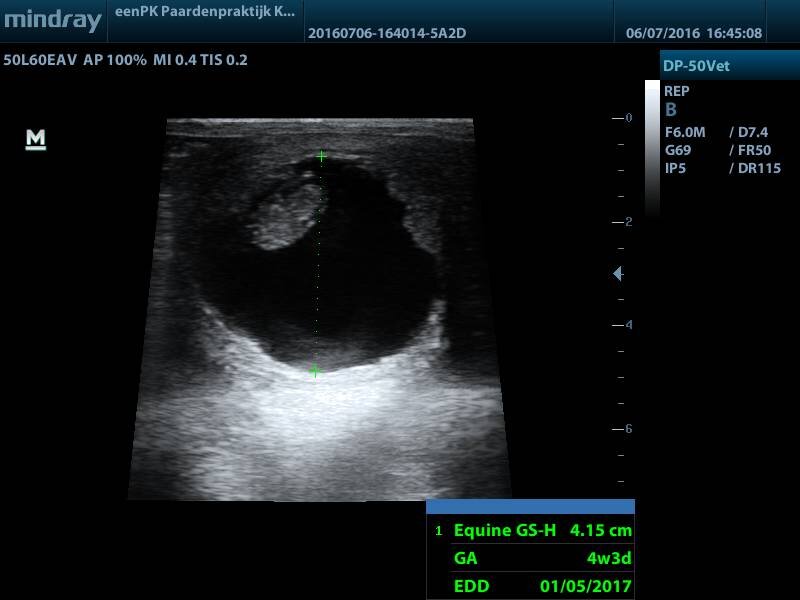

Wauw, wat gaat het goed! Nu de laatste nog, Noa. Bij haar twijfelde ik een beetje al weet ik niet precies waarom. Daar gaan we dan:

Wauw, ook een prachtig baby paardje in de maak te zien!

Uitgerekend: 4-9 mei 2017